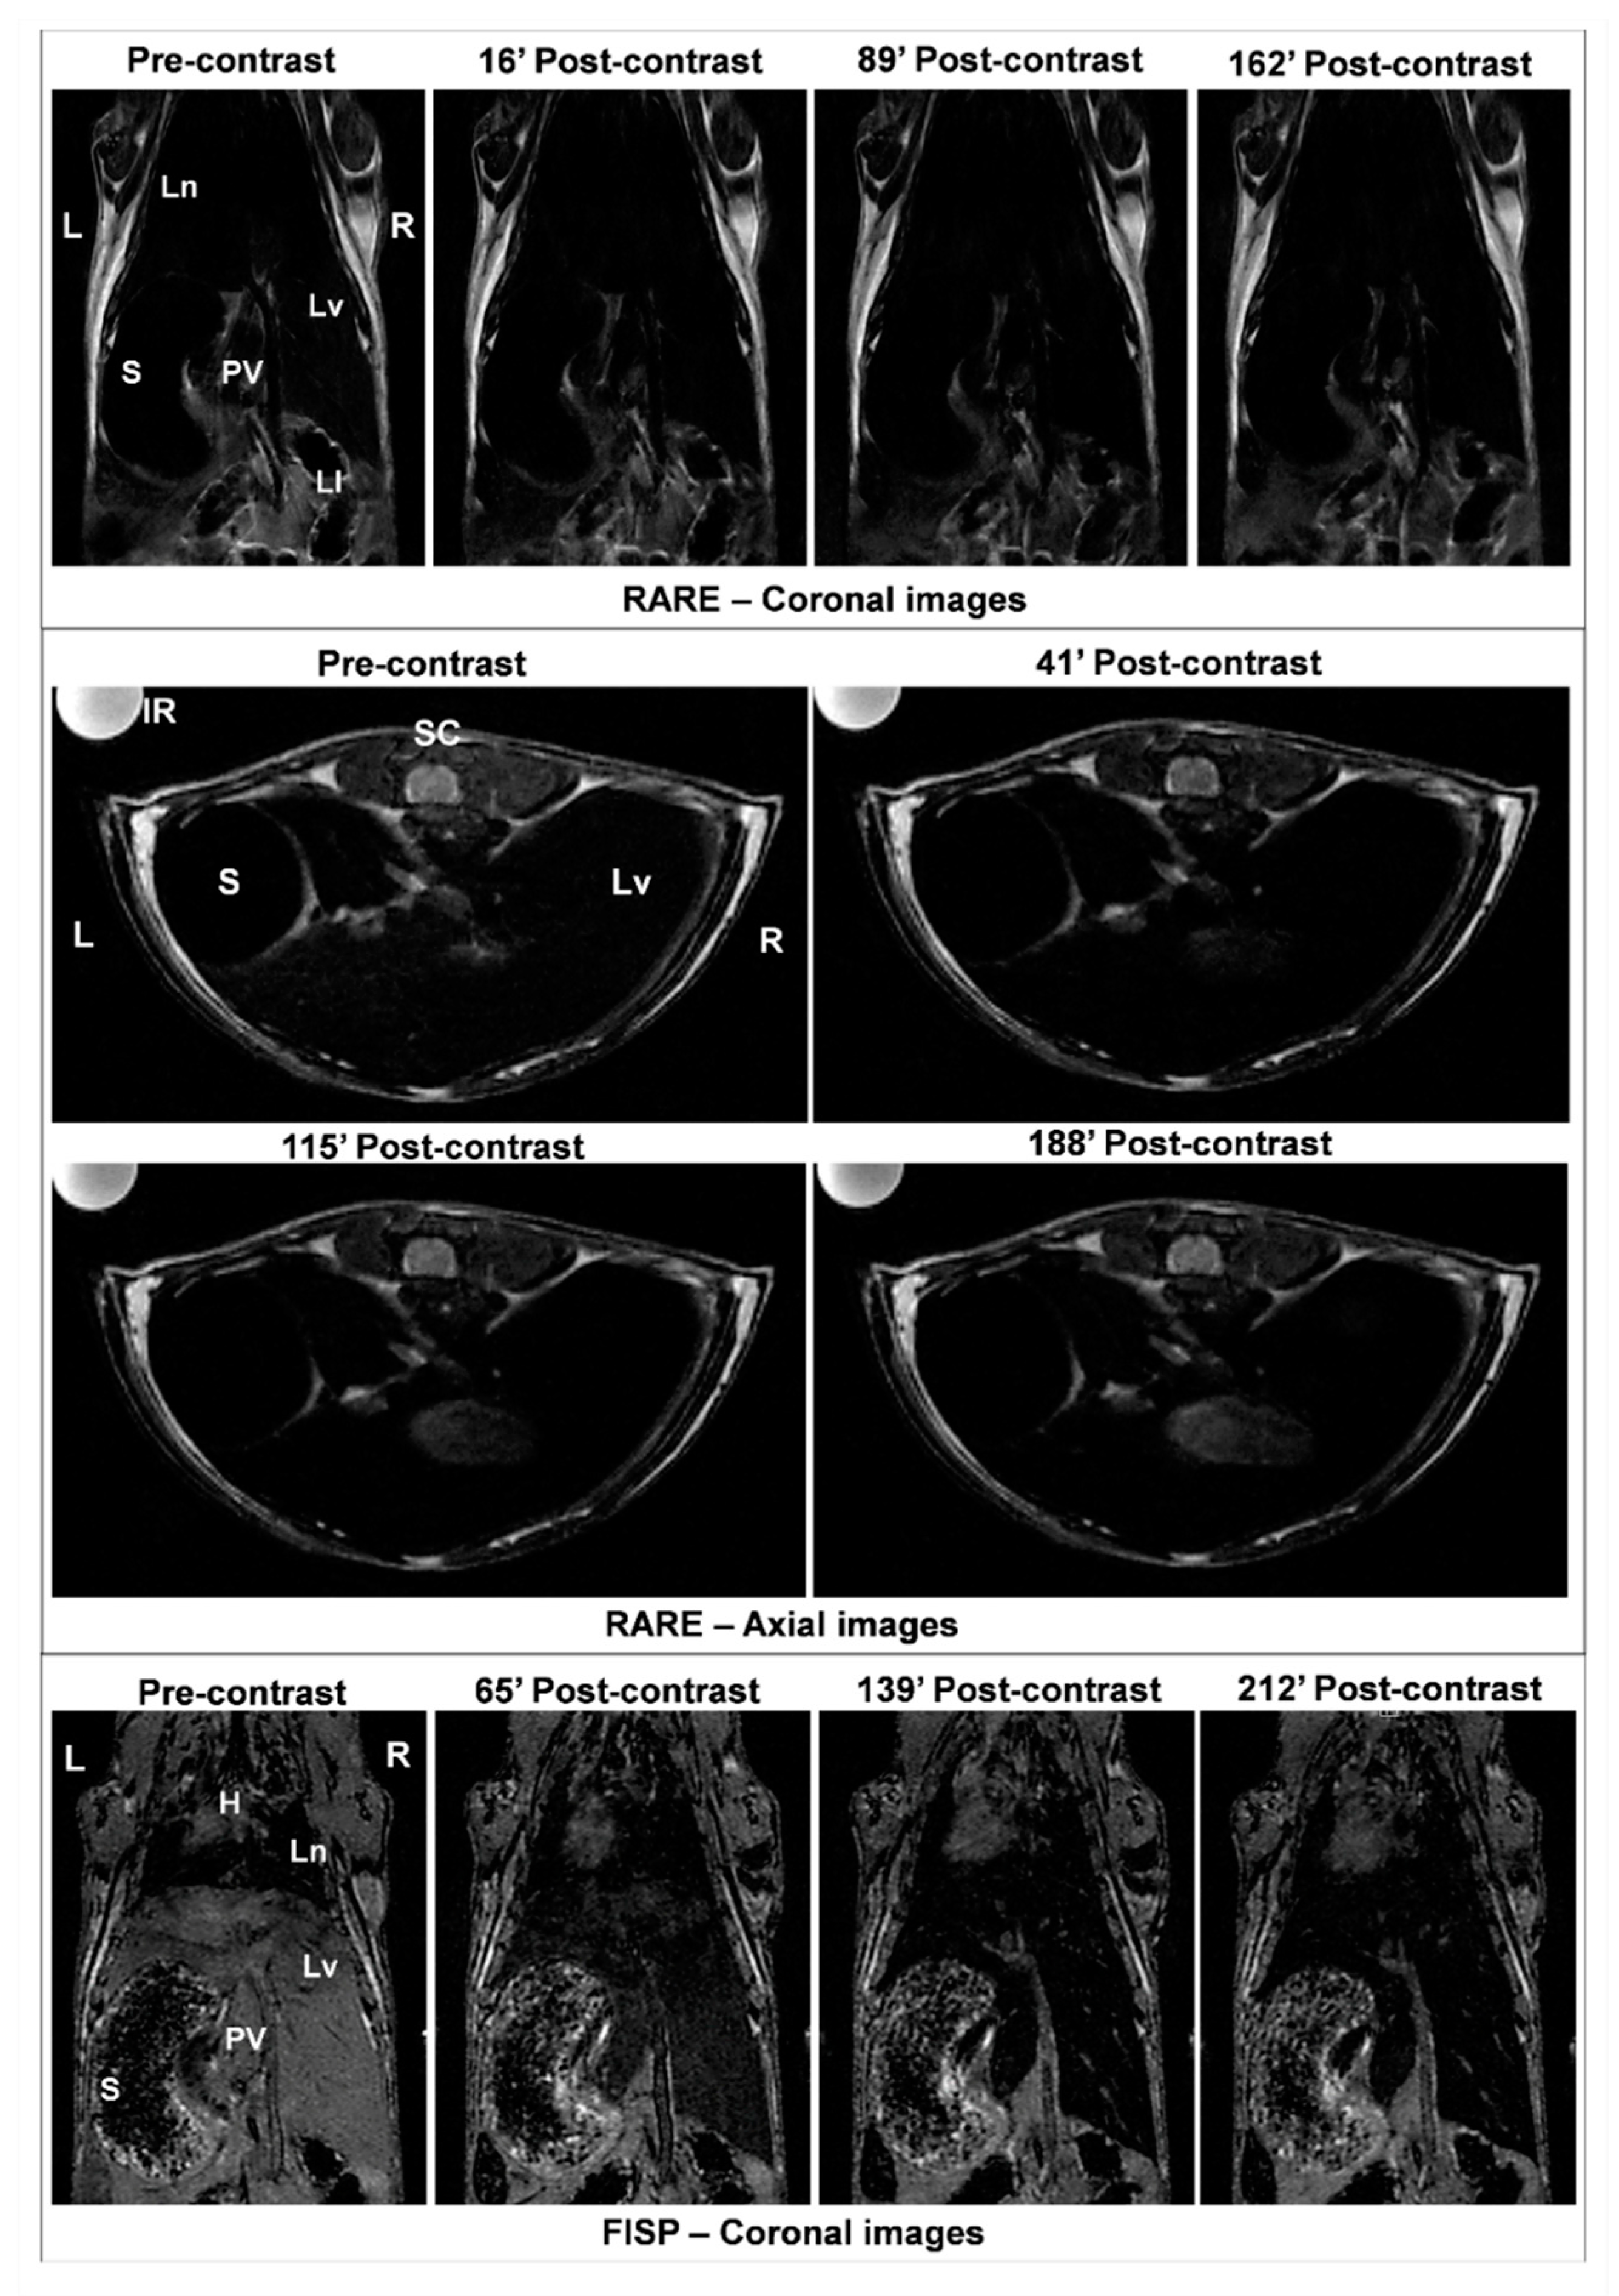

3.3. Efficacy of MNP-DSPE-PEG as Contrast Agents